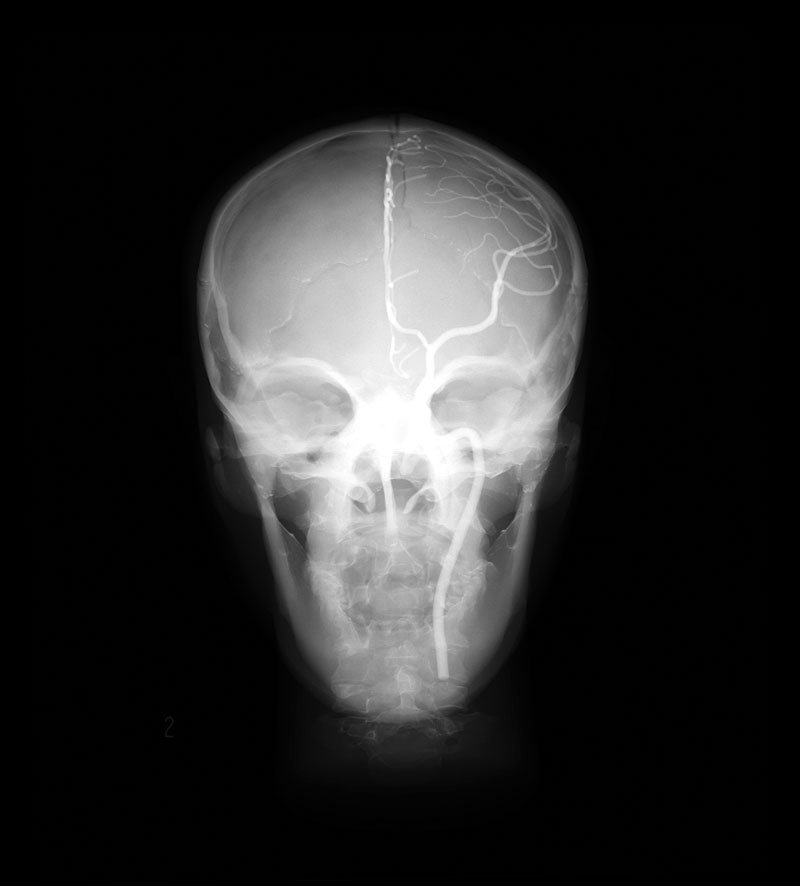

- Dieses Modell besteht aus einem synthetischen Schädel, welcher in einen Kunststoffkopf eingegossen ist.

- In der linken Schädelhälfte sind die vordere und mittlere Hirnarterie nachgebildet und mit Kontrastmittel gefüllt.

- Der Durchmesser der simulierten Arterien reicht von 0,5 mm bis 4 mm.